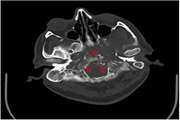

Skull base osteomyelitis: A case report of Garcin syndrome due to mucormycosis in COVID pandemic 1403/12/21 - 09:54